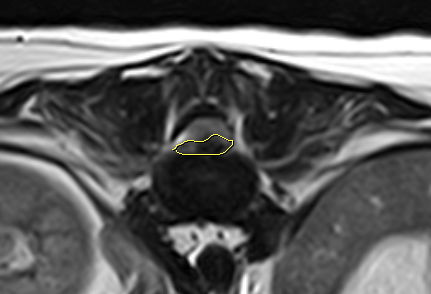

MRI검사를 통해 흉요추 디스크 문제가 원인으로 확인되었습니다.

다발성 흉요추 부위 디스크문제가 확인되었고, 현재 증상을 나타내는 부위를 정확히 진단하기 위한 평가가 진행되었습니다.

이 수술은 디스크 물질을 제거하여 척수를 압박하고 있던 원인을 해소하는 고난도의 수술로, 빠른 의사결정과 숙련된 기술이 필요한 치료였습니다.